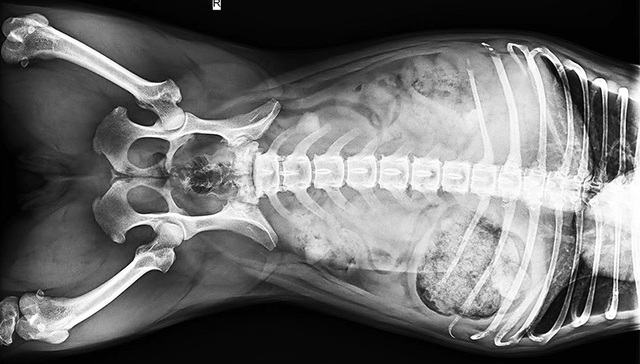

“宠物看病比人看病贵”、“费用不合理”、“过度医疗”......宠物医疗总是饱受争议。据报道,中国城镇养宠用户已超过7000万人,宠物犬猫的数量已经超过1亿只。《中国宠物行业白皮书——2022年中国宠物消费报告》显示,在国内,宠物主花在狗身上的年平均消费大约是2882元,花在猫身上的年平均消费大约是1883元。在宠物的主要消费市场中,医疗排在食品之后,市场份额为29.1%。在医疗之中,诊疗占比最大,其次才是药品、体检和疫苗。

近些年,中医也被应用在了宠物身上。让我们跟随摄影师的镜头,走进宠物诊疗室,一探宠物的看病故事。